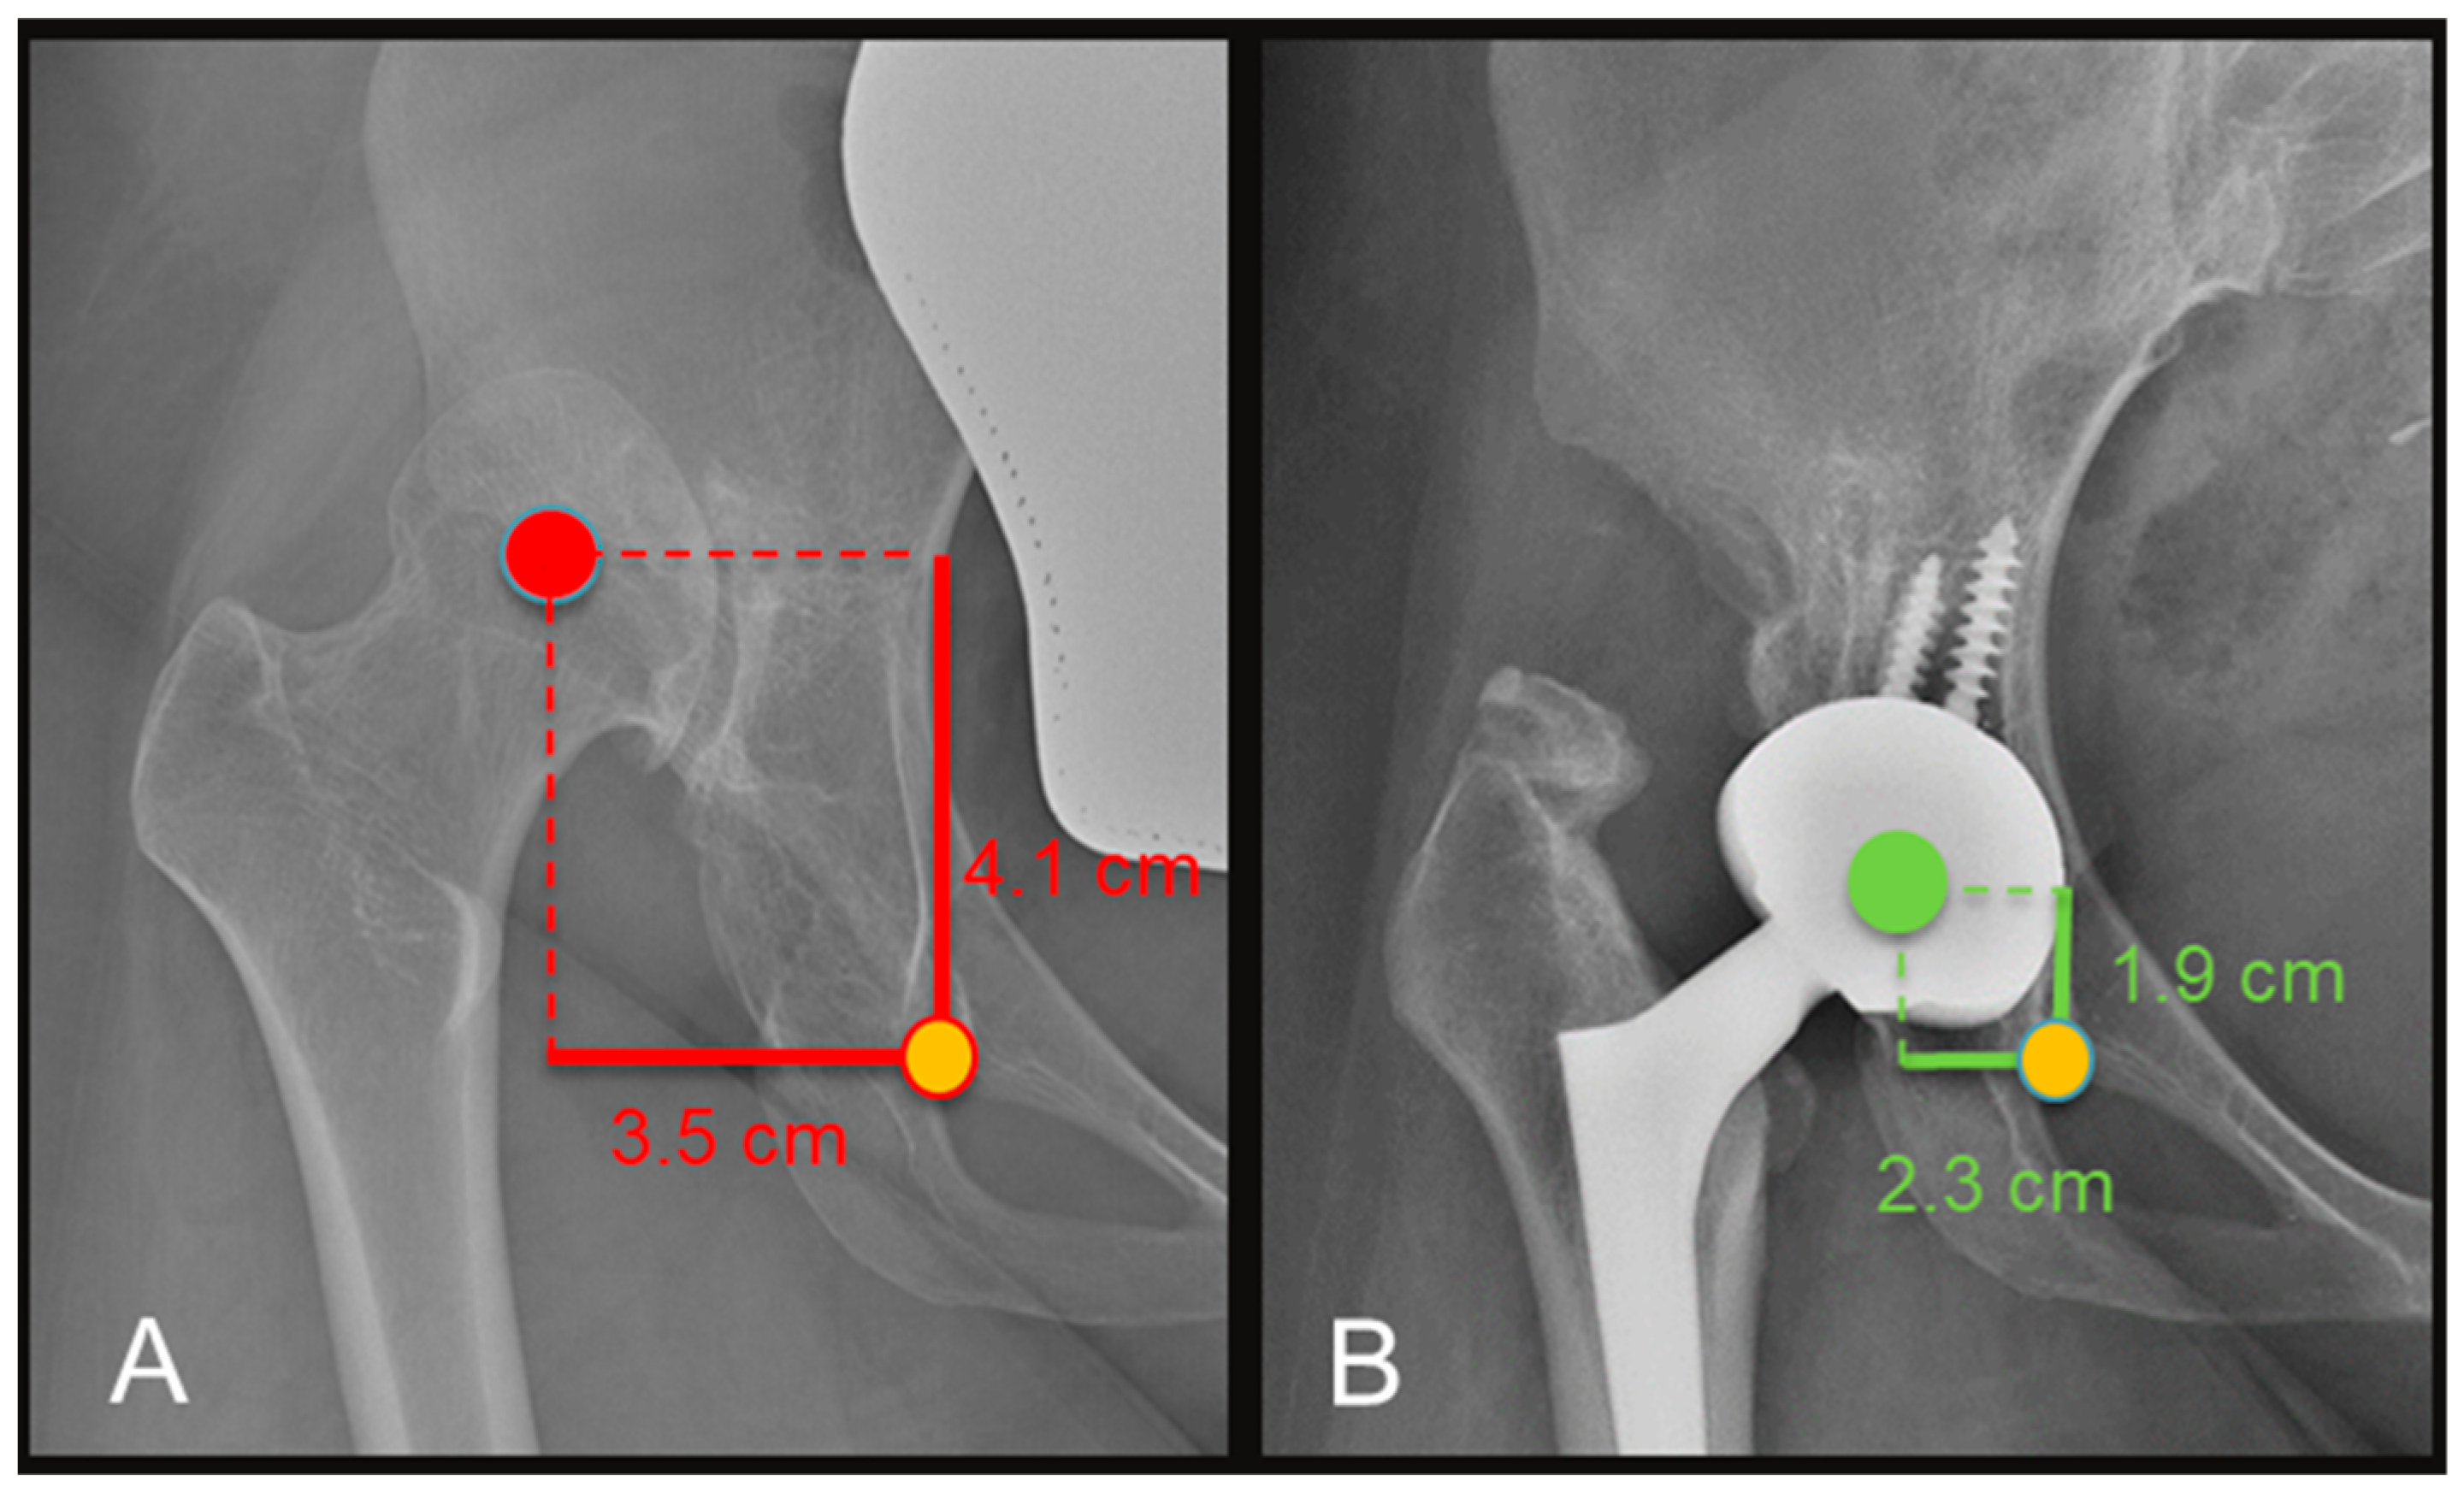

| COR (vertical distance, cm) | 4.6 (2.8–6.6) | 1.9 (1.1–2.4) | <0.002 |

| COR (horizontal distance, cm) | 4.4 (4–4.8) | 2.4 (1.3–3.4) | <0.0003 |